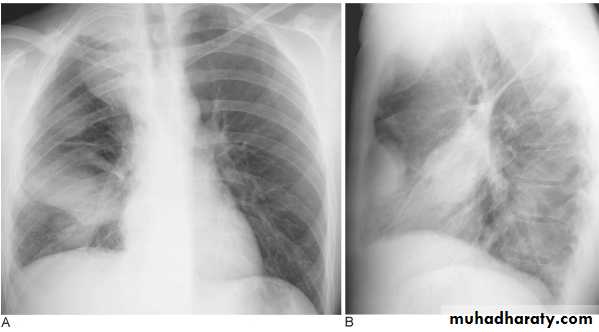

Mycoplasma pneumonia. A 35 year old man presents with nonproductive cough and fever

Lingular consolidation-PA. Patchy effacement of the left heart border.

chest practice

Left upper lobe consolidation-Lat.

The opacification is sited anterior to the obliq- fissure-the position of the upper lobe.